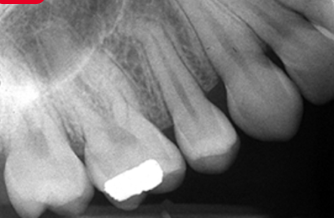

Overlapping Contacts

What it looks like:

Teeth appear stacked on top of each other and you can’t see between them.

Cause:

Incorrect horizontal angulation.

Fix:

Direct the beam through the contact points.